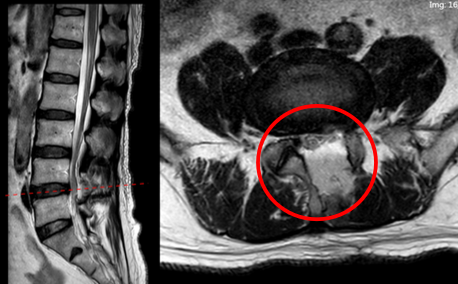

病例三(马尾神经损伤)

男,62岁。

主诉:腰痛伴右下肢疼痛15年、加重1月,间歇性跛行200米。

查体:右侧直腿抬高及加强试验(+)。

手术:L3/4椎板减压+L4/5椎间融合+机器人置钉。

术后:双侧臀中肌腓骨肌无力,会阴区麻木。

术后6周,腓骨肌无力,右踝内翻的状态,右侧臀中肌无力,步行呈现“鸭步”。

思考及建议

出现马尾神经损伤的原因:可能是由于手术器械造成的损伤。

建议:过顶操作应谨慎,并尽可能采用30°镜,同时警惕视野范围外可能出现的器械损伤。